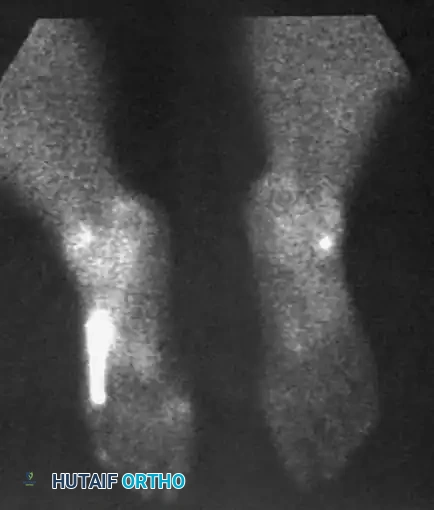

Radiographic examination is indicated to assess for instability, osseous avulsions, and structural alignment. Plain films must be inspected carefully for bone densities in adjacent soft tissues, such as a "fleck sign" indicating SPR avulsion, or proximal migration of the os peroneum indicating a peroneus longus rupture.

While bone scans and computed tomography (CT) can be helpful for osseous pathology, Magnetic Resonance Imaging (MRI) and dynamic ultrasound are the gold standards for soft tissue evaluation. Grant et al. demonstrated the high sensitivity and specificity of ultrasound for evaluating peroneal tendon tears, allowing for dynamic assessment of subluxation. MRI provides excellent visualization of tenosynovitis, tendon morphology, and longitudinal split tears.